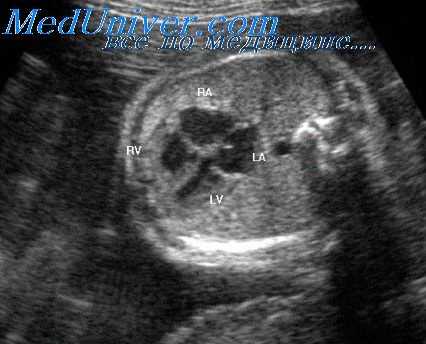

ЭхоКГ при трехкамерном сердце с единственным желудочком

Единственный желудочек при сканировании из апикальной четырехкамерной позиции. Оба предсердия разделены межпредсердной перегородкой, оба атриовентрикулярных клапана расположены в каудальной части межпредсердной перегородки. Они открываются в общий желудочек (V), верхушечная часть которого обозначена звездочкой. Состояние после хирургического сужения легочного ствола (МРА) с помощью синтетической полоски (бэндинга), которая обозначена на эхокардиограмме двумя стрелками. На этом же уровне отмечается турбулентный кровоток. При столь неблагоприятном угле расположения допплеровского датчика определить точно максимальную скорость кровотока по спектральной кривой невозможно (спектральная допплерография в непрерывноволновом режиме).

г) Двумерная эхокардиография. Ценную диагностическую информацию получают при исследовании сердца из апикальной четырехкамерной позиции. С помощью двумерной ЭхоКГ можно уточнить анатомические особенности атриовентрикулярного клапана и тип порока. Расположение и морфологические особенности магистральных артерий и полулунных клапанов лучше видны при исследовании из парастернальной позиции датчика.